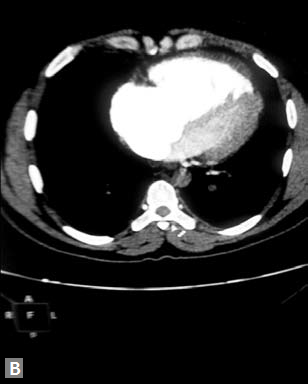

Pericardial effusion may accompany type A dissection.

Hemopericardium is the dreaded complication of leaking

type A dissection (Figs 19S to V). The type B dissection can

cause small foci of atelectasis in adjacent lungs and should

not be mistaken for leak. Type B dissection can leak and cause

left hemothorax.